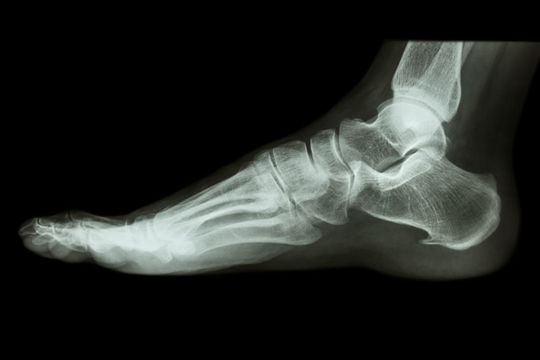

成長期のかかとの痛み

シーバー病は、画像に写る骨に成長線が走り、今にも剥がれそうな状態ですから「原因はこの軟骨部だ」と結論付けます。

しかし、全ての子ども達に異常が確認出来る訳ではありません。

当院へ訪れる子ども達の大部分は骨には異常はありません。

ですから、レントゲンに映る成長骨端核は痛みに関係する程度の事で、引起こす原因では無いと考えても良いでしょう。